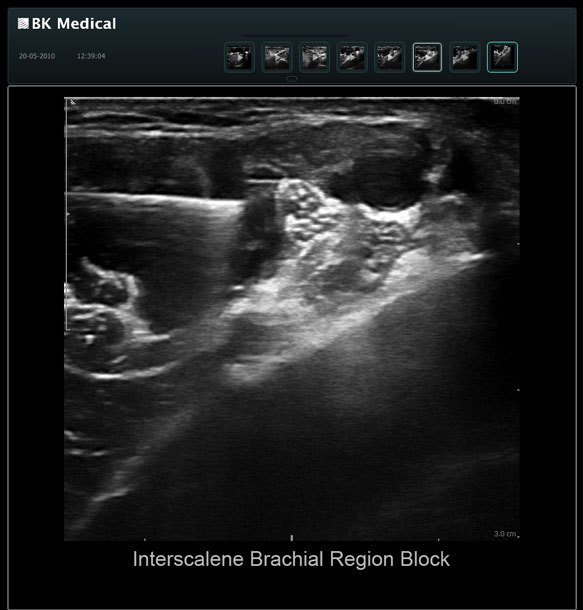

High resolution ultrasound imaging for needle-guided procedures.

The Clearest Image Makes the Clinical Difference for Your Patients

The Flex Focus 400 exp ultrasound system offers premium image quality with fast frame rates for excellent temporal resolution. The system features Automatic Mode Adjustment (AMA) to optimize high resolution B-Mode Imaging when changing modes and depth.

Transducers Designed for Guidance

BK Medical offers high-frequency linear transducers, imaging from 18-2 MHz for upper and lower extremities, and curved array abdominal transducer 8820e for special deep nerves or paravertebral/spinal applications. Our transducers provide superb detail that makes it easy to see your needle during procedures.